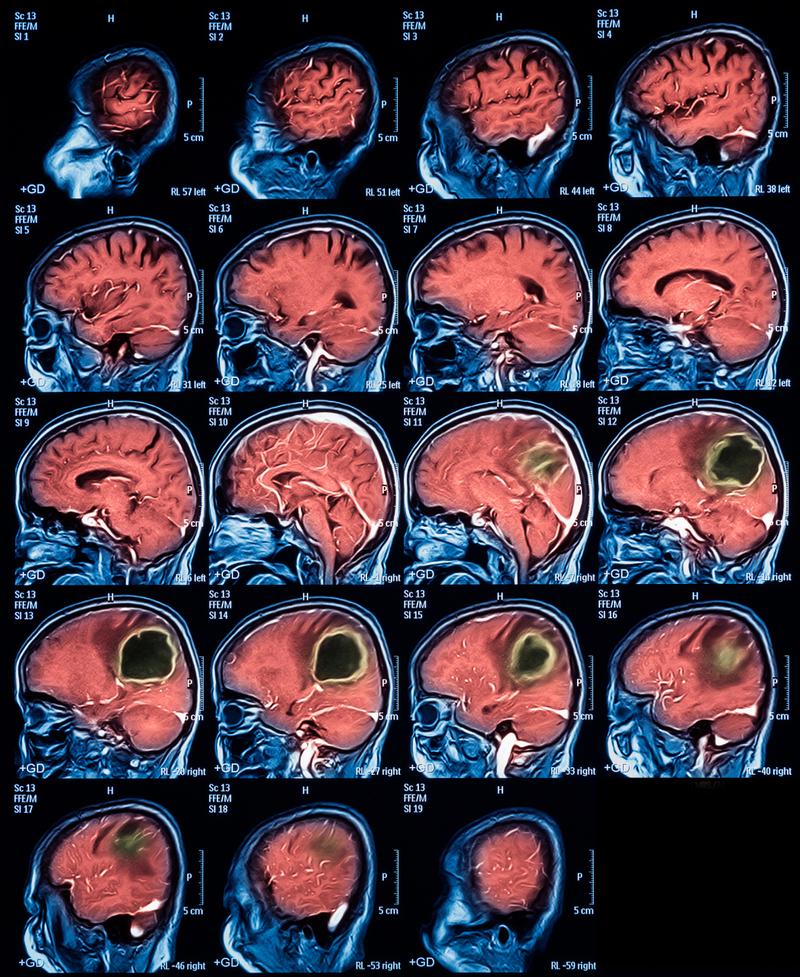

(图片来源网络,侵删)

- 原理:脑梗死后,脑组织会因为缺血缺氧而发生水肿,导致局部脑组织的密度发生改变,通常在梗死后24小时到48小时后,坏死的脑组织会因水分吸收而变得比正常脑组织密度更低,CT图像上会显示为低密度区域。

- 准确性随时间提高:发病6-12小时后,开始有约50%的病例可以被CT发现;24小时后,检出率可高达80%-90%。

- 快速准确:脑出血在CT上表现为高密度(白色)区域,非常清晰,在发病几分钟内就能被准确发现。